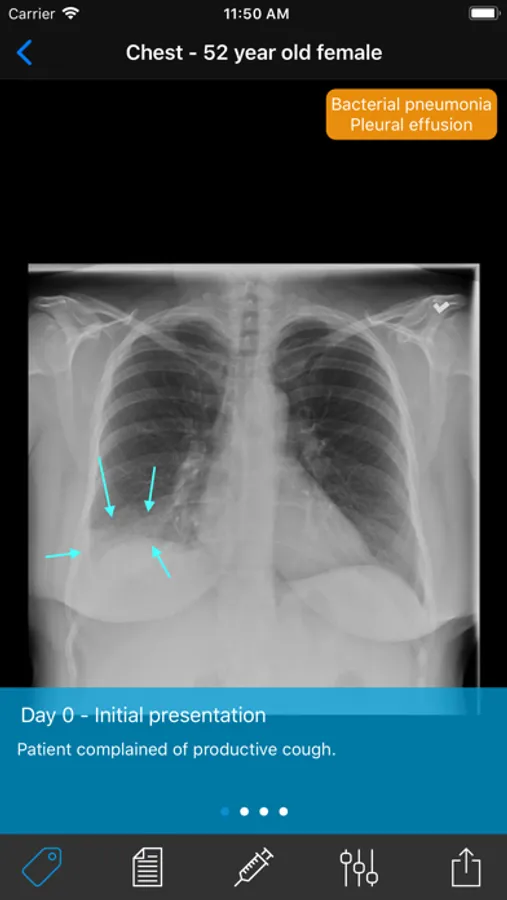

• Real cases with reports, diagnoses, management, and follow-up studies

• Pathologies including fractures, dislocations, infectious disease, cardiopulmonary disease, gastroenterological disease, and many more